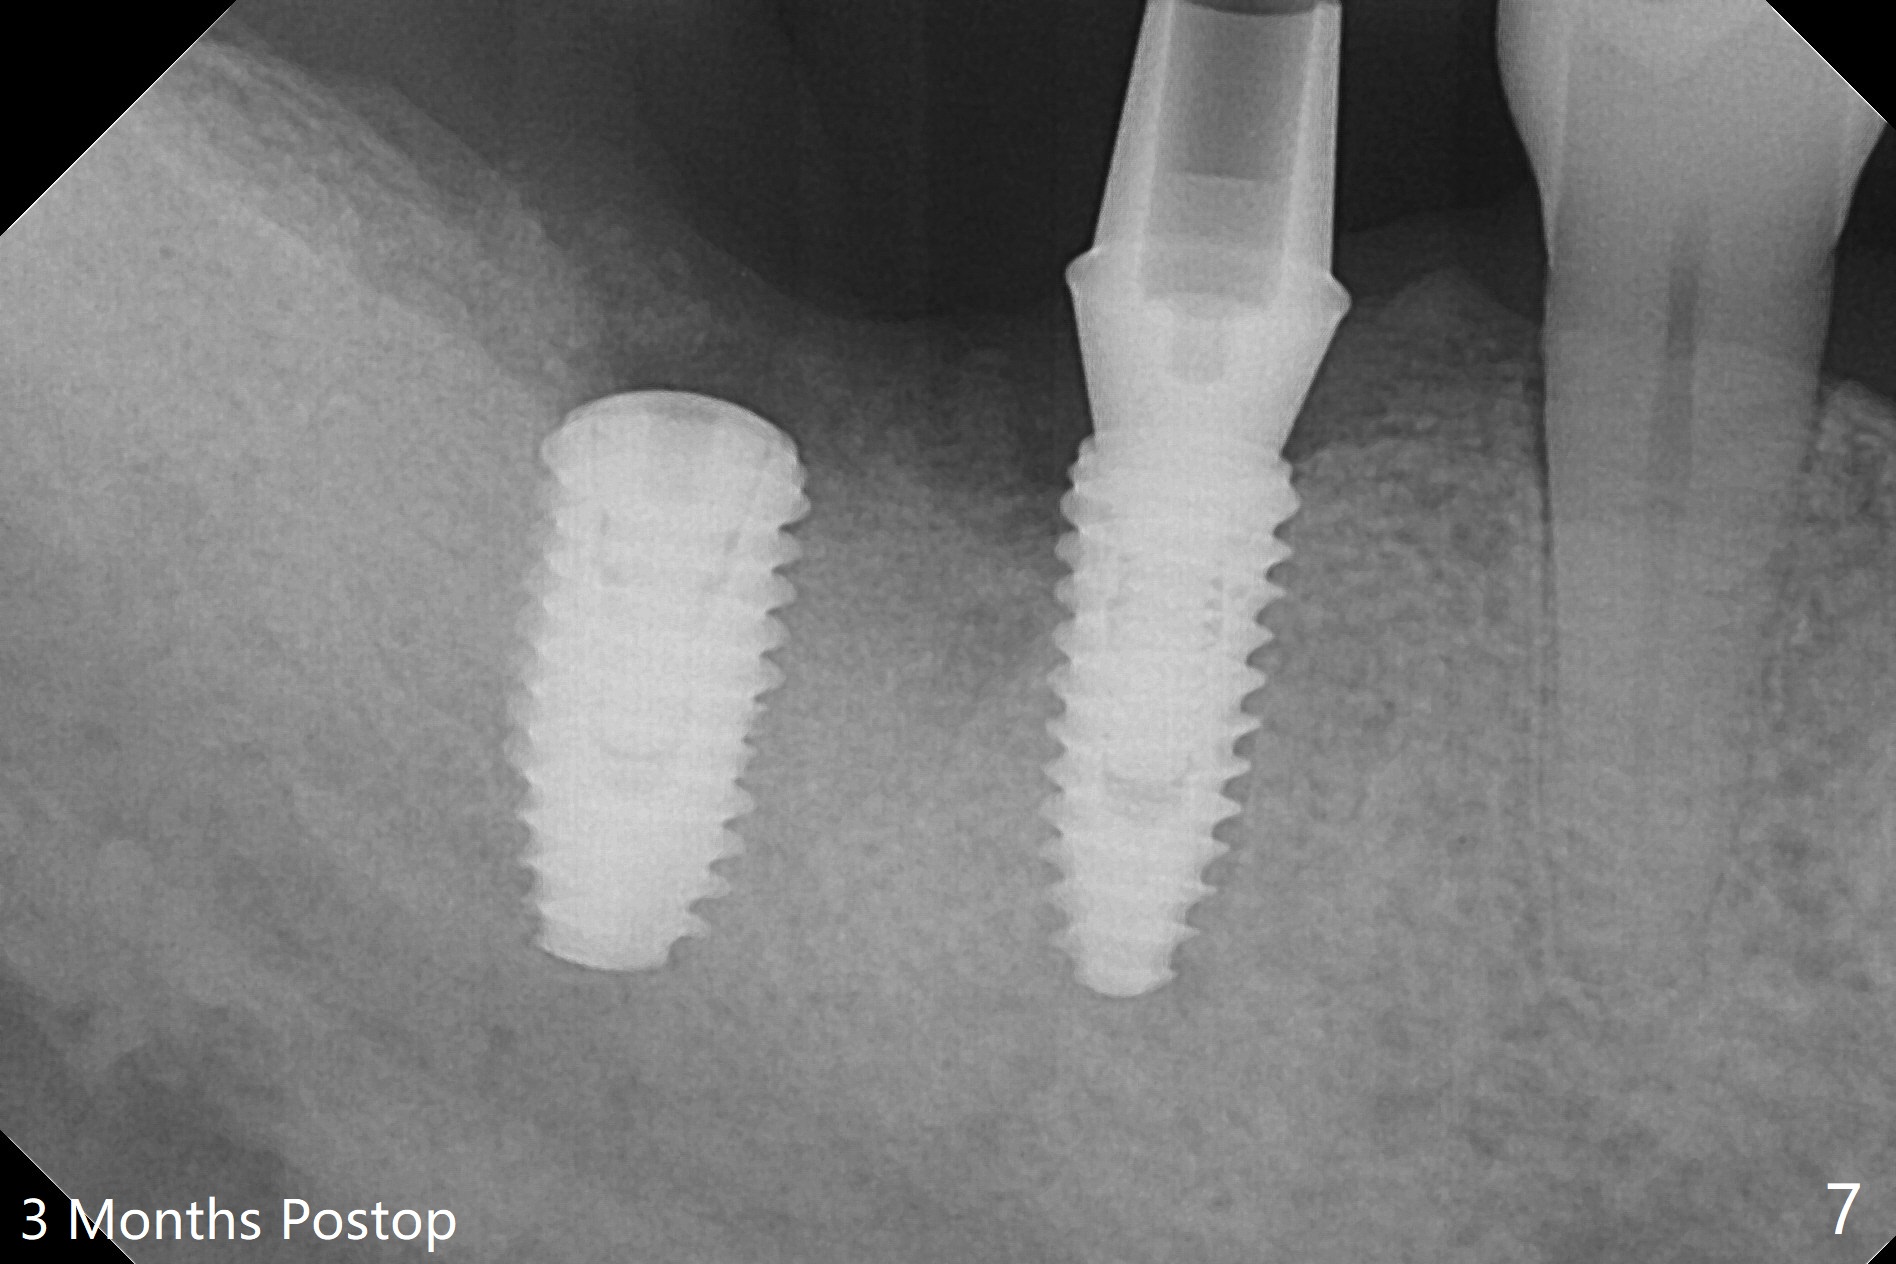

Osteotomy at the sites of #30 and 31 is initiated with Magic Split, followed by Magic Expanders (3.0 and 3.8 mm) at #31. Initial depth of osteotomy is 13 mm with 2.2 mm drill (Fig.1). After adjustment of the trajectory at #31 (Fig.1 arrow) and deepening the osteotomy by 2 mm, dummy implants are placed with stability (Fig.2). Following increase in osteotomy at #31, the larger implant in fact loses stability (Fig.3). The loose implant is pushed distal (Fig.4 arrow) with placement of autogenous bone mesial (*). The stable implant at #30 (Fig.3) and its abutment (Fig.4) are used as a post to hold periodontal dressing, which covers the wound at #31 after placement of collagen plug and suturing. In fact the same technique could be used when socket preservation was performed if an implant were placed at #30 at the same time. When the periodontal dressing dislodges, the wound at #31 heals uneventfully (Fig.5,6). The bone graft seems to remain in place 3 months postop (Fig.7). The implant is uncovered with placement of a 6.8x7 mm healing abutment 4 months postop. When a cementation abutment is placed and prepped, the buccal margin is much lower than the lingual (Fig.8 taken prior to cementation). The patient enjoys mastication with the new implant crowns 3.5 months post cementation (Fig.9).